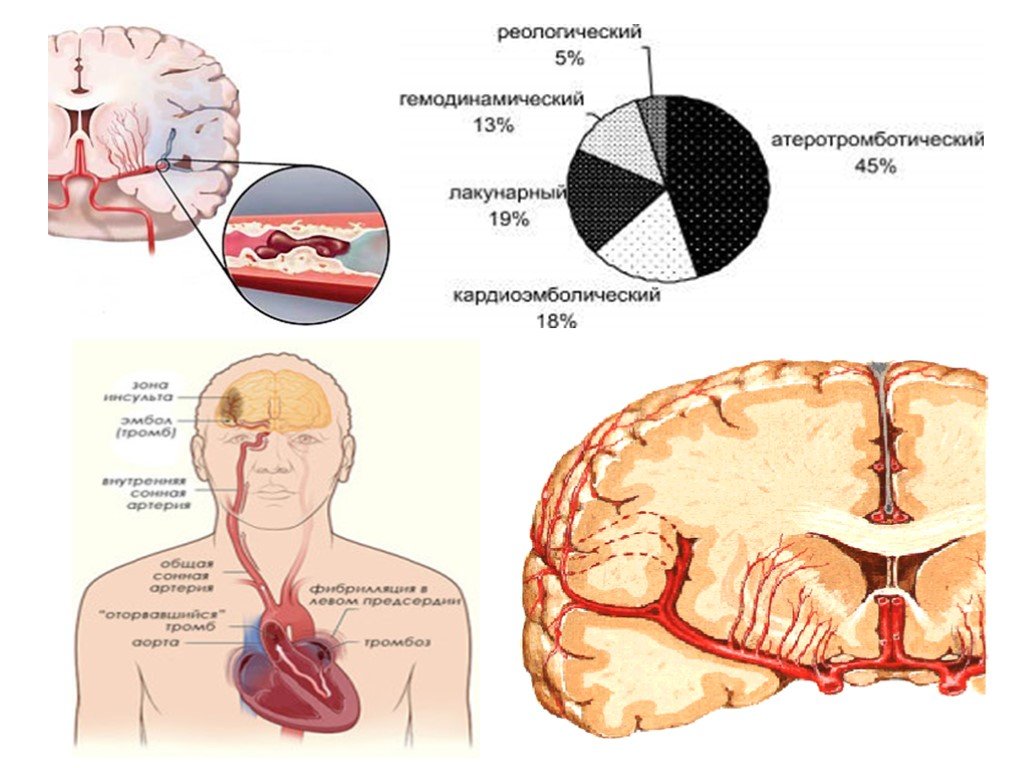

Хроническая ишемия головного мозга и лейкоареоз: симптомы и лечение